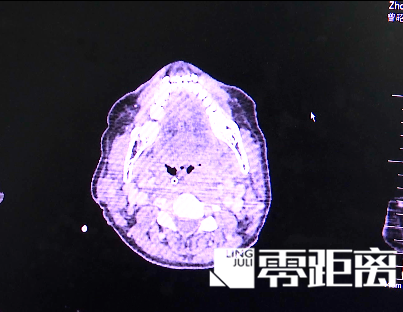

冰镇止痛的方法在医学上并不稀罕。在临床中,比如做扁桃体手术,经常让病人含服一些冰水或者吃冰棒、冰敷,一定程度上可减轻疼痛。